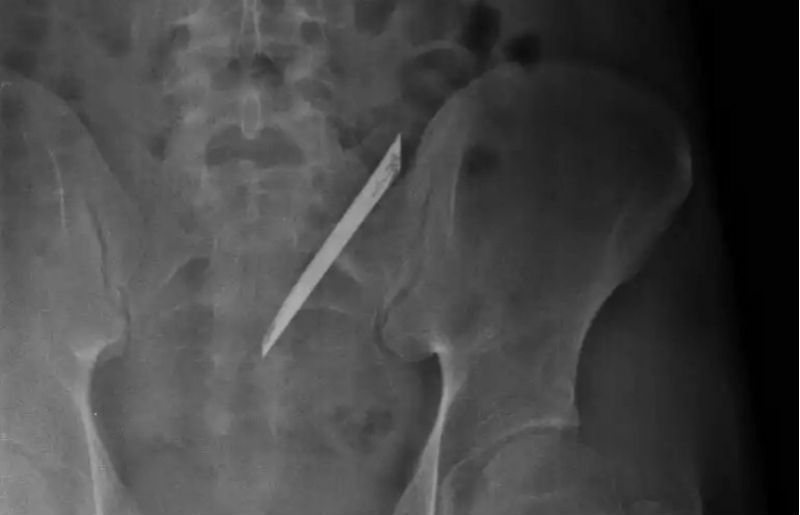

| Lưỡi dao dài 12 cm qua hình chụp CT scan |

Ê-kíp bác sĩ khoa Ngoại tổng quát bệnh viện Nhân Dân 115 (TP.HCM) vừa phẫu thuật lấy lưỡi dao Thái Lan dài 12 cm nằm trong lưng 4 năm của anh Quang (tên bệnh nhân được thay đổi, 24 tuổi, ngụ quận 6).

Trước đó, anh Quang thấy đau lưng kéo dài nên tới cơ sở y tế chụp CT scan thì phát hiện có dị vật bên trong.

Nam thanh niên sau đó tới bệnh viện 115 phẫu thuật lấy dị vật là lưỡi dao nhọn ra ngoài.

Anh Quang kể, 4 năm trước anh có xảy ra xô xát với một nhóm thanh niên rồi bị đâm trúng. Ở bệnh viện địa phương, anh được bác sĩ khâu vết thương rồi cho về vì thấy vết thương không nghiêm trọng, cũng không chụp phim X-quang.

Theo bác sĩ khoa ngoại tổng quát, đây là trường hợp hi hữu. Lưỡi dao dù đã nằm lâu năm trong cơ thể người bệnh nhưng không đâm vào cột sống, nên không ảnh hưởng đến thần kinh.